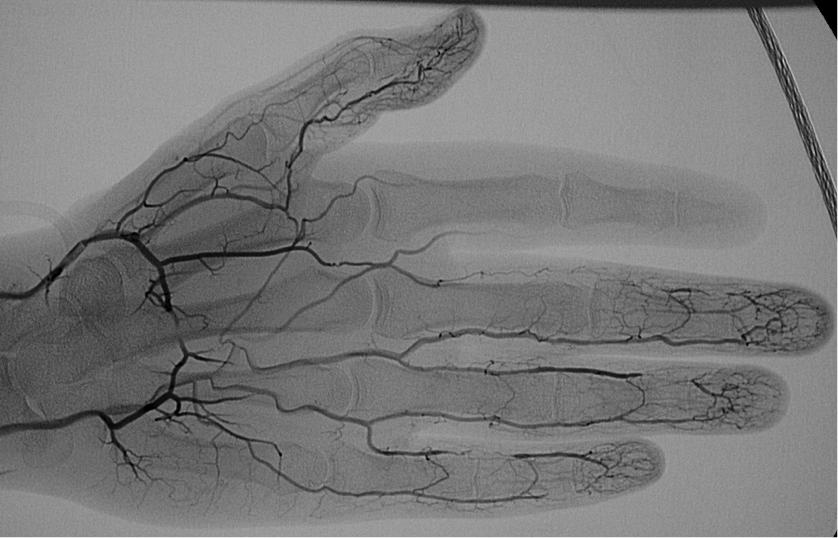

What is this a picture of? What disease?

Why is it important?

Vasculopathy associated with scleroderma.

Impt to note that the Raynaud’s assocaited with scleroderma is a vasculopathy, not a vasculitis.